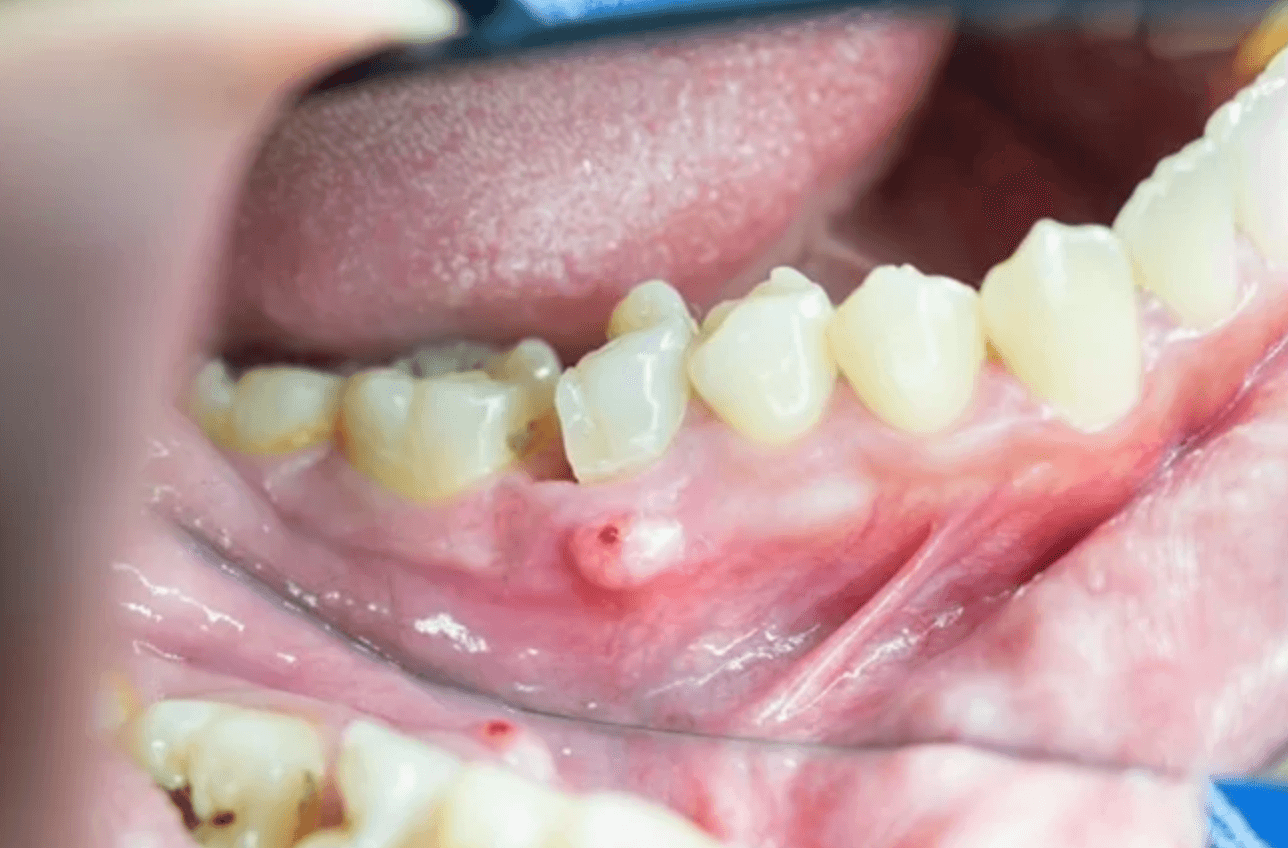

치근단 농양

글쓴이 같은 경우 치근단 농양으로 현재 2개의 임플란트를 하였으며, 하나는 치근단절제술로 몇개월 잘 유지되는가 싶더니 다시 염증이 잇몸을 뚫고 나와 현재 다시 치근단절제술을 할지 아니면 뽑고 임플란트를 할지 고민을 하고 있습니다.

이처럼 치근단 농양은 치료를 한다고 모두 정상으로 돌아오는게 아닙니다. 다시 재발하여 염증이 차오를 수 있으며, 결국 치근단절제술도 통하지 않아 치아를 발치하고 임플란트를 해야 됩니다.

치근단 농양 증상

- 만성적 잇몸 누공 발생

치근단 농양 수술 후기

치근단 농양 치료 수술은 치근단절제술이라고 하여, 치아뿌리를 절단하여 더 이상 염증이 나오지 않게 치료하는 것입니다. 이러한 치료를 하였다고 하여 100% 성공이 되는 것이 아니기 때문에, 재발할 가능성 또한 높습니다.

글쓴이 또한 이번에 재발하여 다시 재수술을 하자니 치근단절제술 하기가 생각보다 쉽지 않고 통증이 생각보다 심했습니다. 저는 염증이 심해서 뼈를 많이 녹여서 뼈이식을 했는데 얼굴이 거이 1주일 이상 부어 있었거든요.

수술 후에도 잇몸이 아직도 크라운 쪽으로 100% 내려오지 않아 약간 치아와 잇몸사이 구멍이 있어 자세히 보면 정말 보기가 싫습니다. 그래서 차라리 이번에 그냥 뽑아버리고 임플란트로 할까 그런 생각도 드는데, 최대한 살려보고자 치과 의사와 현재 고민 중인 치아입니다.